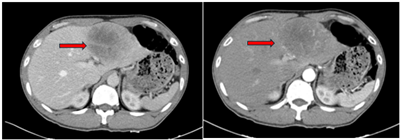

Ca lâm sàng: Điều trị ung thư biểu mô tế bào gan bằng thuốc điều trị đích Sorafenib tại Trung tâm Y học hạt nhân và Ung bướu, Bệnh viện Bạch Mai.

Ung thư biểu mô tế bào gan (hepatocellular carcinoma –HCC)  là loại ung thư thường gặp đứng thứ hai theo ghi nhận của Tổ chức Globocan Việt Nam năm 2022, ước tính mỗi năm có 24,502 trường hợp bệnh...